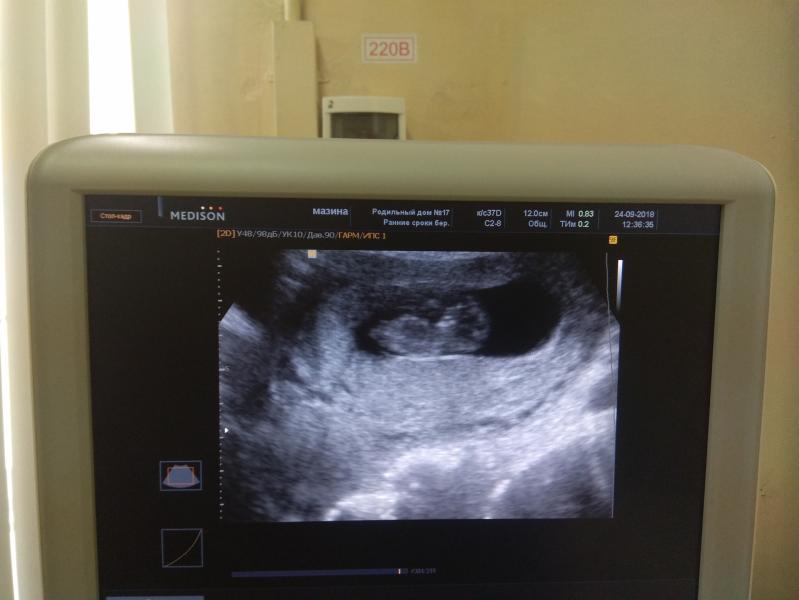

Наш малыш. Уже очень хочется узнать кто это. Доча сегодня с большим интересом смотрела на монитор и наблюдала как он шевелится)))

#2018 #ЕлизаветаЕвгеньевна #Исенины #детиэтосчастье #детицветыжизни #доча #люблюнемогу #10недель

@elena2760 я не на 100% уверена, что девчушка) но вот этот маленький отросточек прямо лежит, у ребят он под углом 30° вверх вздёрнут.

Я тоже девочку вижу по половому бугорку) сообщите потом😍 интересно

@tatiana.zolushka.vetrova @iv_any мальчик)) у нас сынок